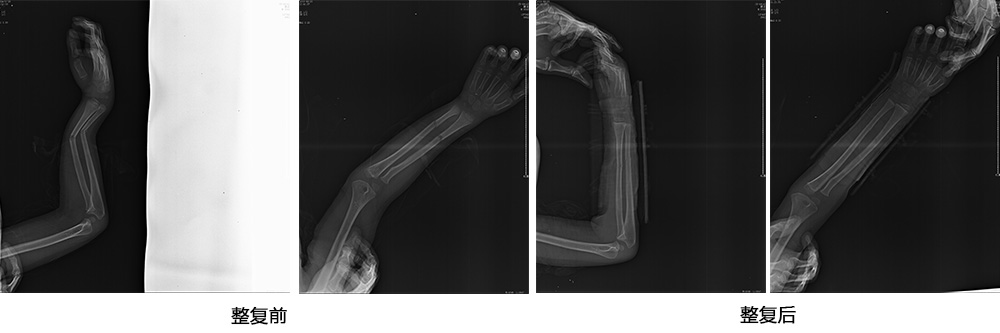

傳統(tǒng)手法整復(fù)病例影像